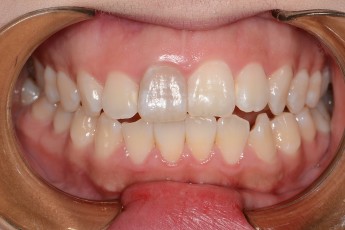

Before

After